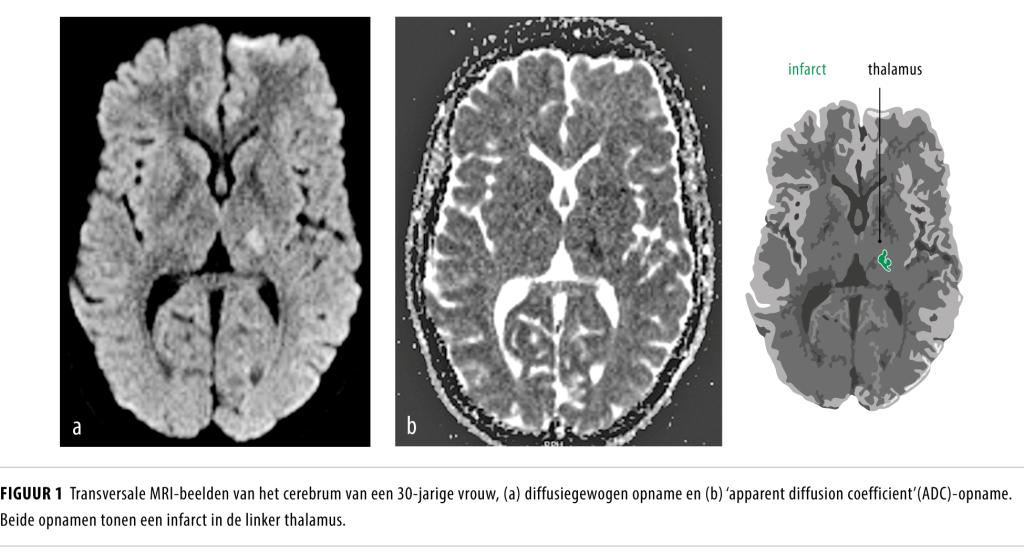

Een 30-jarige vrouw zonder klassieke vasculaire risicofactoren kwam op de SEH met acuut ontstane tintelingen in de rechter lichaamshelft, verminderde kracht in haar rechter arm en wazig zien met beide ogen. Zij was 29 weken zwanger van haar eerste kind. Bij neurologisch onderzoek vonden wij hypesthesie van de rechter lichaamshelft en een geringe piramidale parese met ataxie van de rechterarm. MRI van het cerebrum en MR-angiografie toonden een thalamusinfarct links (figuur 1), zonder onderliggende vaatafwijking. Het ecg, de 48-uursholsterregistratie en een transthoracale echo van het hart toonden geen afwijkingen. Gezien haar zwangerschap kreeg zij monotherapie met acetylsalicylzuur in plaats van clopidogrel. Inmiddels heeft zij na een ongecompliceerde bevalling een gezonde zoon. Wij konden geen duidelijke oorzaak voor het herseninfarct vinden. Mogelijk heeft een verhoogde stollingsneiging in het derde trimester een rol gespeeld. Wij adviseerden na de bevalling over te stappen van acetylsalicylzuur op clopidogrel.